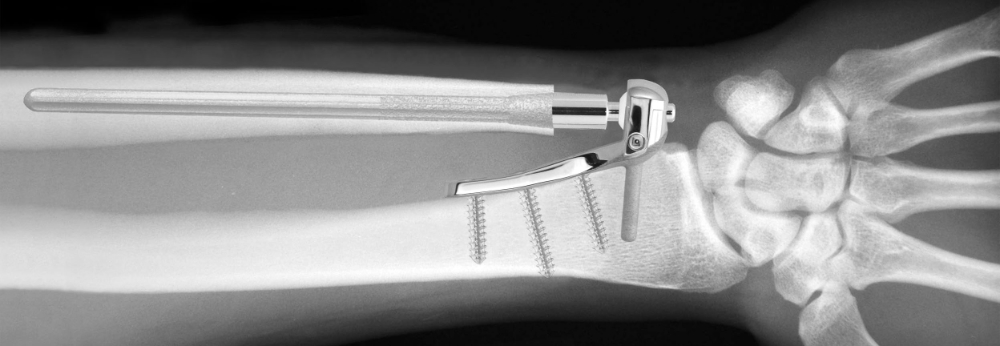

Prothèse Scheker

pour l'articulation radio-ulnaire distale

• La prothèse se compose d'une plaque radiale, d'une tige cubitale, d'une boule en polyéthylène de masse molaire très élevée (UHMWP), d'un couvercle de plaque radiale et d'une goupille transversale de verrouillage.

• La plaque radiale remplace la fonction de l'apophyse styloïde radiale.

• La tige cubitale et la boule remplacent la fonction de la tête cubitale.

• Le couvercle de plaque radiale et la goupille transversale de verrouillage remplissent la fonction du ligament triangulaire du carpe (TFCC).